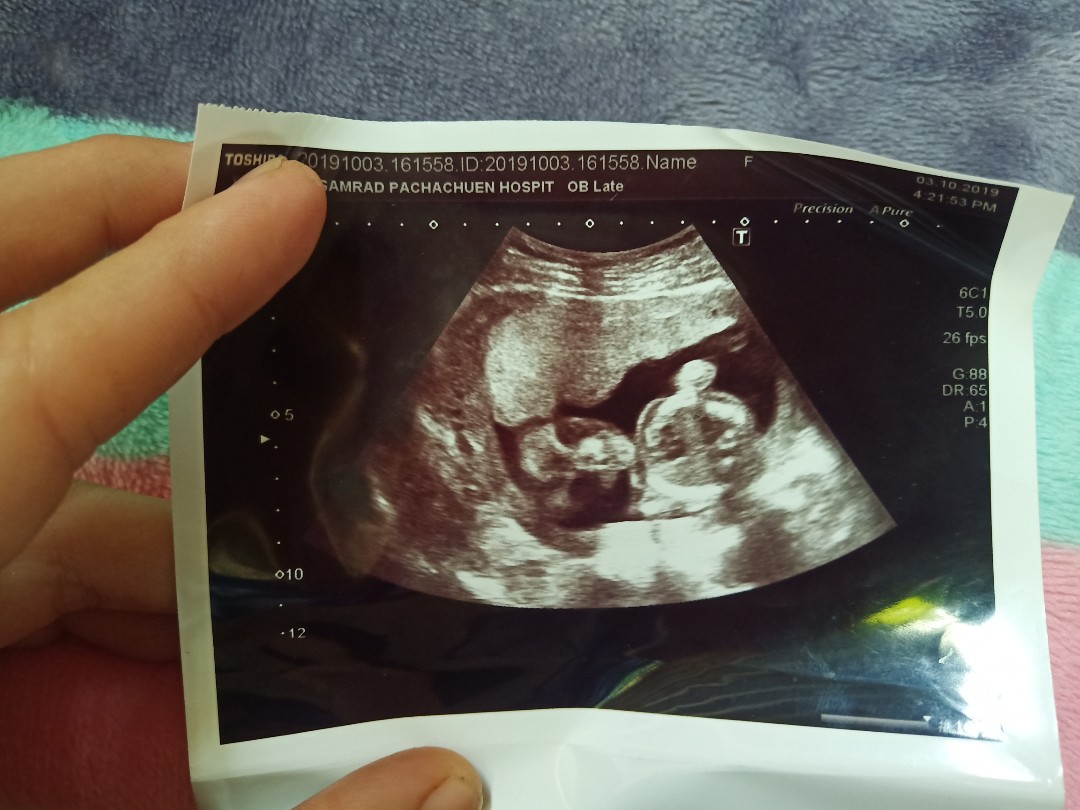

กำหนดคลอดซาวตอน7 wหมอให้กำหนดคลอด8/3/63 ภาพนี้ซาวประมาณ18w หมอให้กำหนดคลอดใหม่3/3/63 ปัจจุบันตอนนี้20w จ้าน้องเป็นผู้หญิง